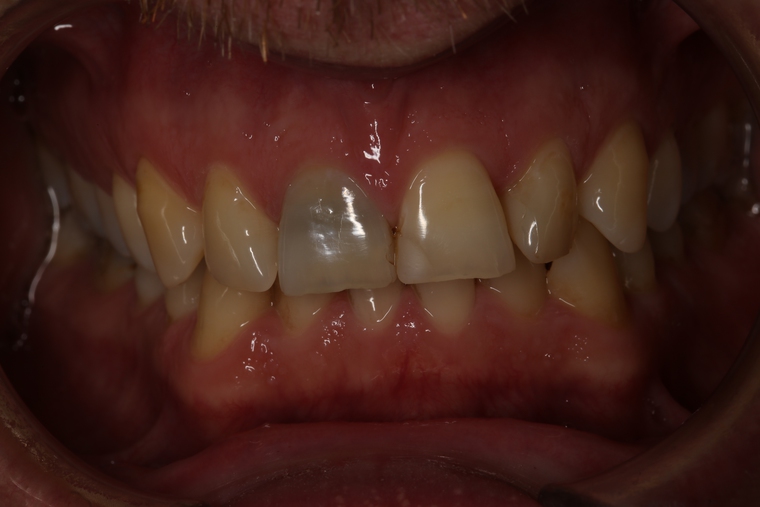

Ein Tätigkeitsschwerpunkt unserer Praxis in Salzburg ist die Implantologie. Wenn ein Zahn fehlt oder entfernt werden muss, sollte immer die Möglichkeit der Implantation im Vordergrund stehen. Ein Implantat verhält sich von den Eigenschaften genau so wie ein natürlicher Zahn. Egal ob nur ein einzelner Zahn vom Zahnarzt ersetzt werden muss oder ein ganzer Kiefer mit festsitzendem Zahnersatz versorgt werden soll, wir finden für Sie eine Möglichkeit, auch wenn die Voraussetzungen ausweglos erscheinen. Wenn möglich versorgen wir unsere Patienten mit Keramikimplantaten. Diese sind immun-neutral und können sehr oft direkt bei der Zahnextraktion eingesetzt werden. Für unsere Patienten ist daher meist nur ein operativer Eingriff notwendig!